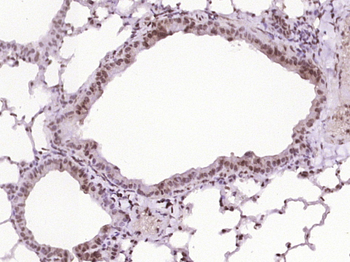

应用稀释比例:IHC-P=1:100-500, IHC-F=1:100-500, IF=1:100-500, Flow-Cyt=1ug/test, ELISA=1:5000-10000